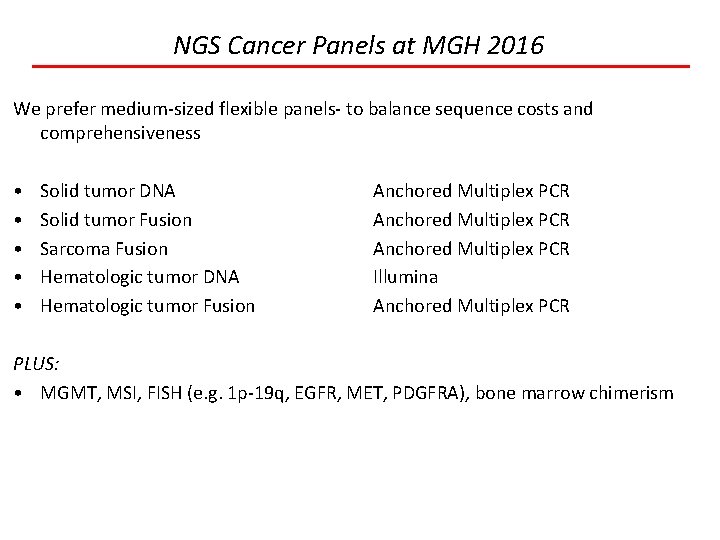

NGS Cancer Panels at MGH 2016 We prefer medium-sized flexible panels- to balance sequence costs and comprehensiveness • • • Solid tumor DNA Solid tumor Fusion Sarcoma Fusion Hematologic tumor DNA Hematologic tumor Fusion Anchored Multiplex PCR Illumina Anchored Multiplex PCR PLUS: • MGMT, MSI, FISH (e. g. 1 p-19 q, EGFR, MET, PDGFRA), bone marrow chimerism